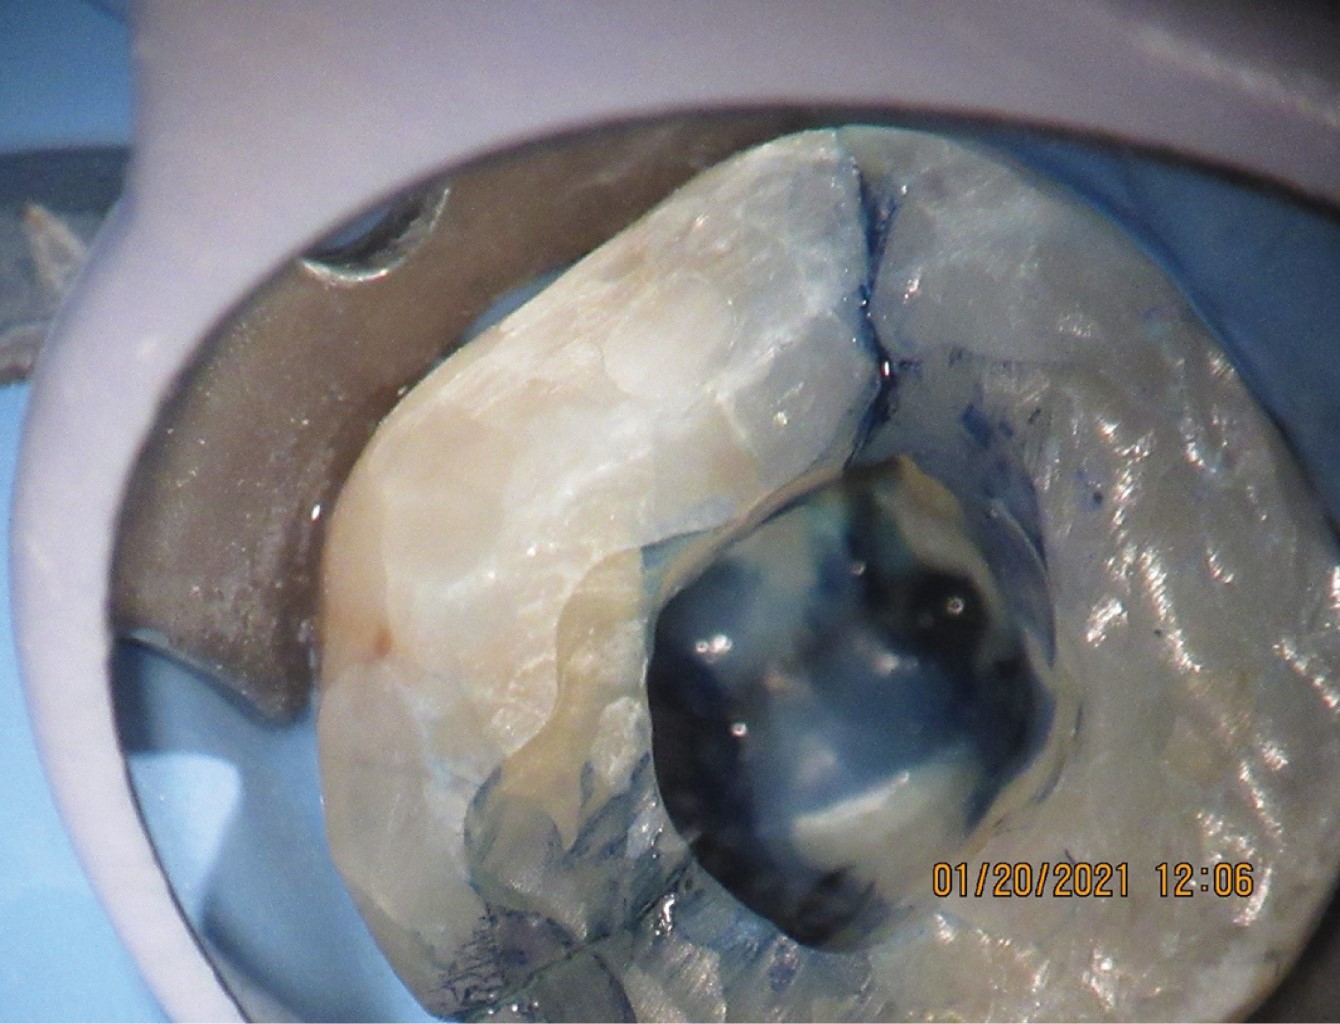

Figure 1

Figure 2

Figure 3

Figure 4